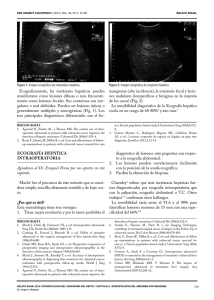

Ecograficamente, las metástasis hepaticas pueden manifestarse